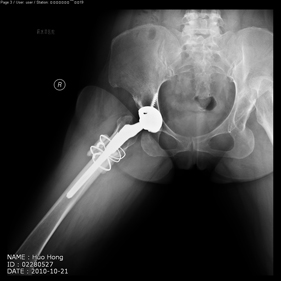

Department of Adult Joint Reconstructive Surgery

shortening osteotomy and total hip replacement for bilateral severe dysplasia of hip with high riding